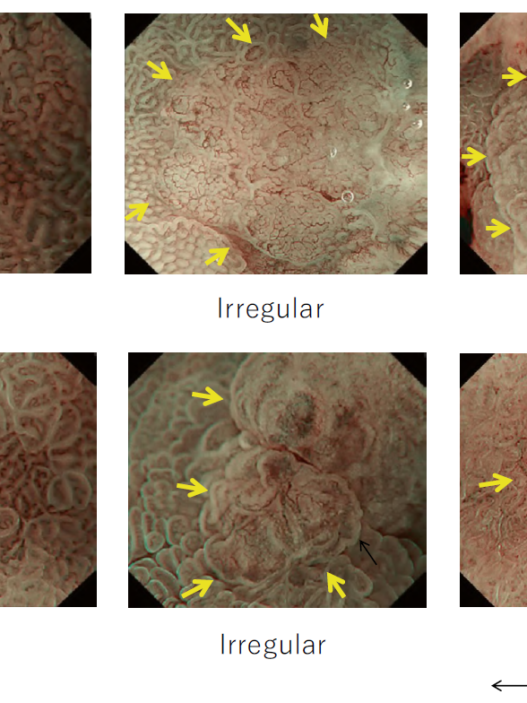

Between the late 1980s and early 1990s, research on image processing and analysis was conducted mainly by the National Cancer Center Hospital East and Olympus Group, which led to basic experiments on narrow band light imaging starting in 1994. As a result, a patent application was made in 1999, and a narrow band imaging (NBI) device (Olympus Co., Tokyo, Japan) was introduced commercially in 2006. Since the early 2000s, it has been demonstrated by a number of researchers that NBI is useful for early diagnosis of cancers of the oropharynx, hypopharynx, esophagus, stomach, and large intestine. A succession of similar techniques was later made public, and interpretation of the term “special light observation” began to differ among academic societies and research organizations. In view of this problem and the need to establish internationally applicable terminology for endoscopy, we proposed an object-oriented classification for endoscopic imaging in 2008. Basically, the concept was that endoscopic imaging can be divided into five categories: (1) conventional endoscopy (white light endoscopy (WLE)), (2) image-enhanced endoscopy (IEE), (3) magnified endoscopy, (4) microscopic endoscopy, and (5) tomographic endoscopy [1].

IEE is subdivided into optical, digital, optical-digital, and chromoendoscopy methods.

While NBI has spread and contributed to the standardization of diagnosis on a global level, our colleagues have worked tirelessly to further improve the quality of endoscopy. Over the last 15 years, owing to the development and worldwide spread of NBI, international classifications have been introduced in the field of gastric cancer, Barrett’s esophagus, and colorectal neoplasia.

Since the introduction of this classification, several IEE techniques have become commercially available through advances in endoscopy technology, including blue light imaging (BLI), linked color imaging (LCI), red dichromatic imaging (RDI), and texture and color enhancement imaging (TXI). Therefore, a revised version including those techniques is presented in Fig. 1.